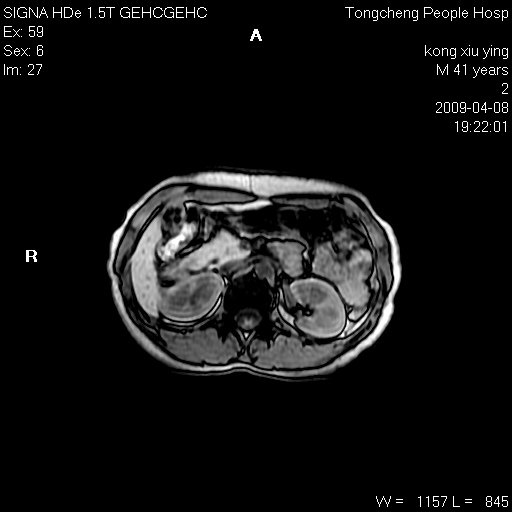

标题: CL1008:【经典】胆囊石榴籽样结石。

女,41岁。健康体检——彩超提示:胆囊显示不清。平素健康,无不适感。

腹部mr扫描及mrcp,图像如下:

标题: 胆囊阴性结石ct图片

好啊!我有ct的插进来啊,楼主请允许噶。